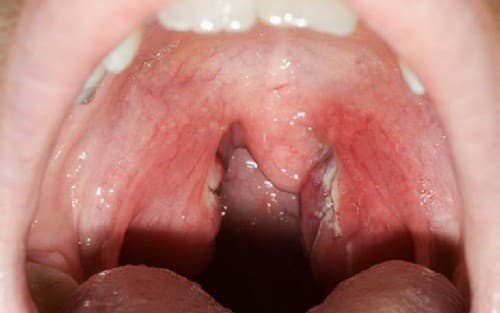

- Quan sát bằng mắt thường cũng có thể thấy có mủ trắng ở amidan, họng sưng đỏ